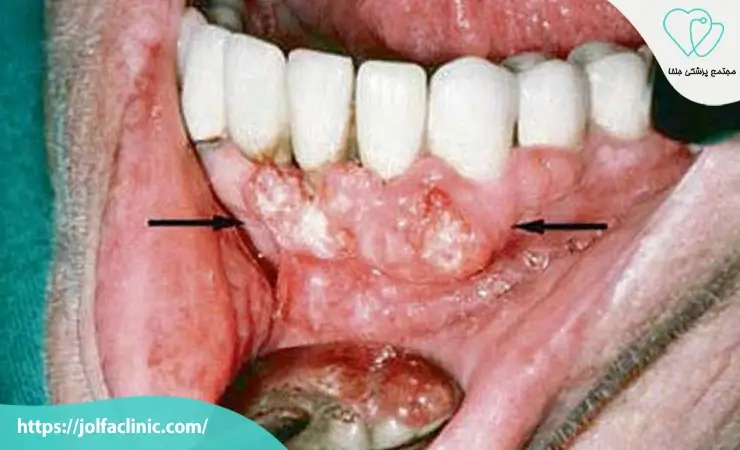

کیست ها در صورت رشد ممکن است بخش زیادی از استخوان را تخریب کرده و باعث ضعف ساختاری شوند. برداشتن کامل این ضایعات ضروری است تا از بازگشت آن ها جلوگیری شود. تشخیص زود هنگام کیست یا تومور می تواند روند درمان را ساده تر و نتایج را قابل اعتمادتر کند.